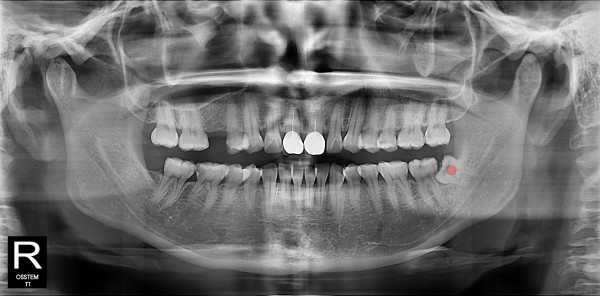

사랑니발치 30대/여성

5e20e086184bc11a2d853605b7813944_1764319714_5316.jpg